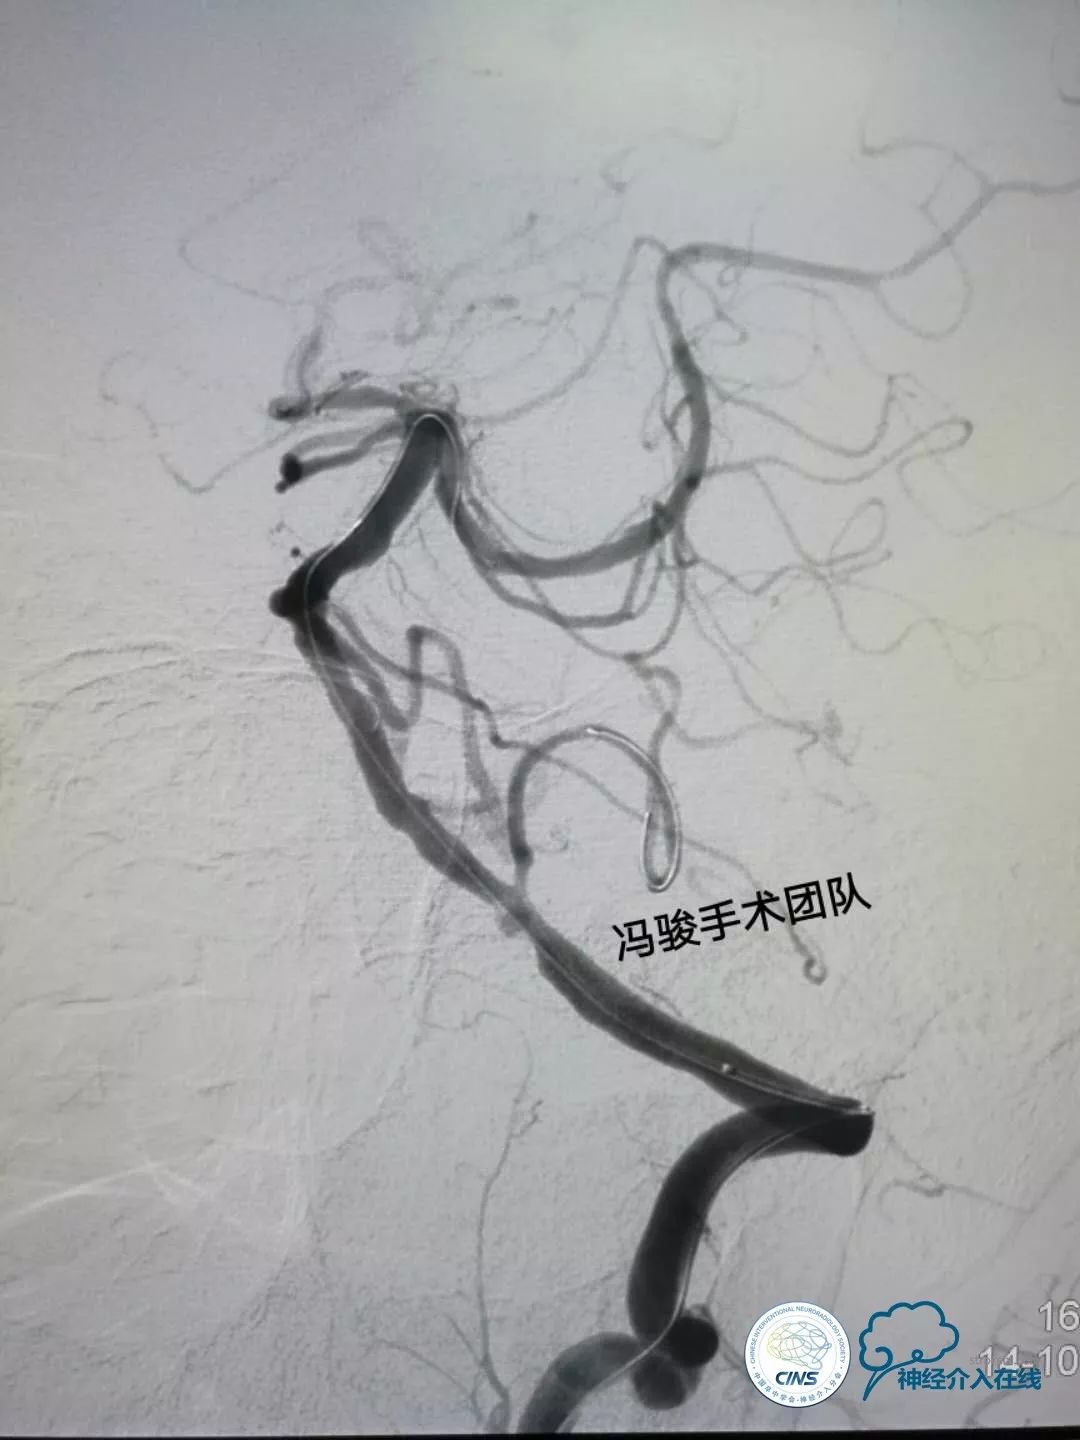

全麻下,将6F的envoy通过左椎动脉V1迂曲段,置于V2段远端,使用双导丝保护技术,1根微导丝置于左侧大脑后动脉,另1根置于左PICA。

缓慢预扩,5-10秒递增一个大气压,先用1.5mm球囊预扩左PICA,再用2.5mm球囊预扩左椎V4段病变处,再次造影显示狭窄均明显改善,血流顺畅。

留置PICA保护导丝,于左椎动脉V4段释放3.0mm-15mm,apollo支架,PICA会被压闭吗?

回答3

再次造影,显示左椎动脉V4段狭窄解除,双侧大脑后动脉及左PICA均血流通畅。